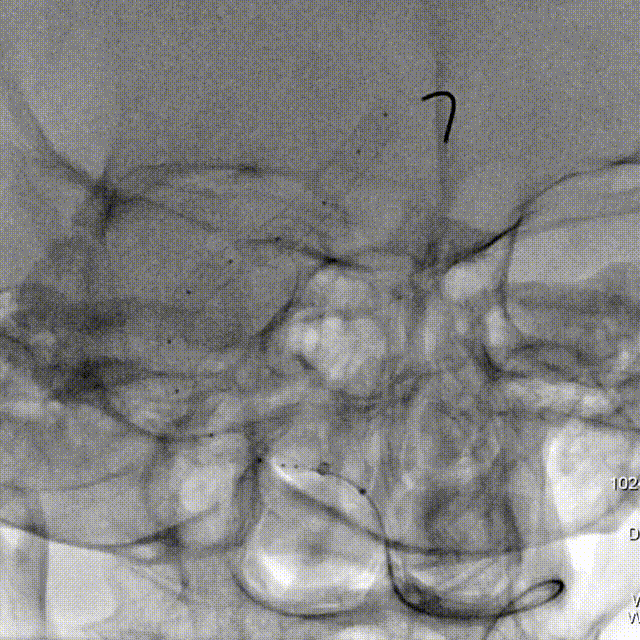

桡动脉入路:

Lattice支架输送:

微导管到位。

支架输送,整体回拉定位。

Lattice头端释放:

支架头端打开。

造影避开对侧椎开口。

Lattice中段释放:

继续释放支架中段。

造影显示中段贴壁良好。

Lattice完全释放:

完全释放支架解脱。

造影显示整体打开贴壁良好。

术后即刻造影: